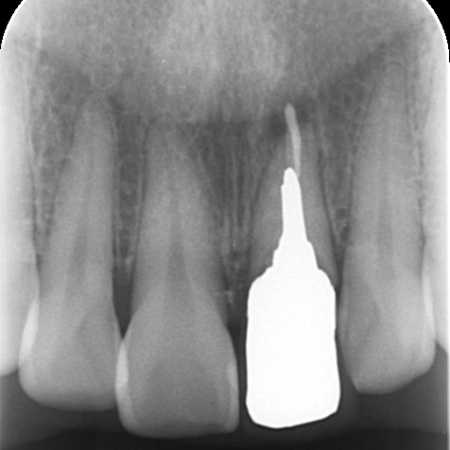

またレントゲン撮影をして詳しく検査したところ、左上前歯が細菌感染を起こしており、歯根の先端に膿が溜まっていることが判明しました。歯の土台となっている金属のメタルコアも、長期保存が不可能な状態です。

抜歯部位の隣の歯は健康であるため、ブリッジよりもインプラントのほうがほかの歯への影響が少ないこと、抜歯と同時にインプラントを埋める「抜歯即時埋入インプラント」であれば治療期間が短縮できることを説明し、インプラントによる治療に同意いただきました。

まずは左上前歯にエクストリュージョンを行い、歯と歯茎の境目を整えたうえで抜歯を行います。抜歯と同時にインプラントを埋め込み、治療中の審美性を考慮して仮歯を装着しました。